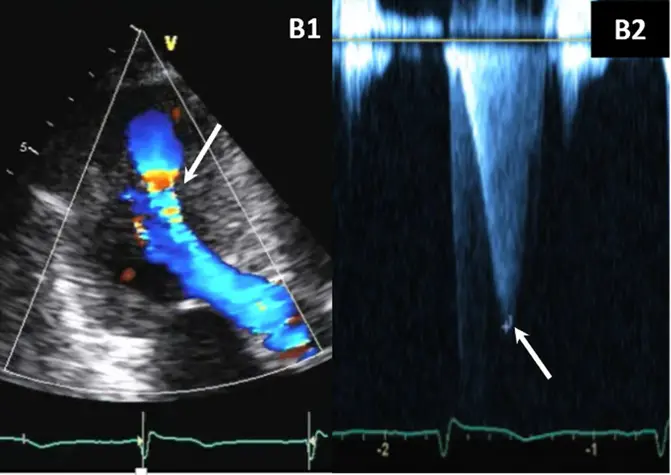

- Color-flow Doppler shows turbulence at mid-ventricular level

- CWD typically shows a narrow, late-peaking systolic velocity (“ice pick” appearance)